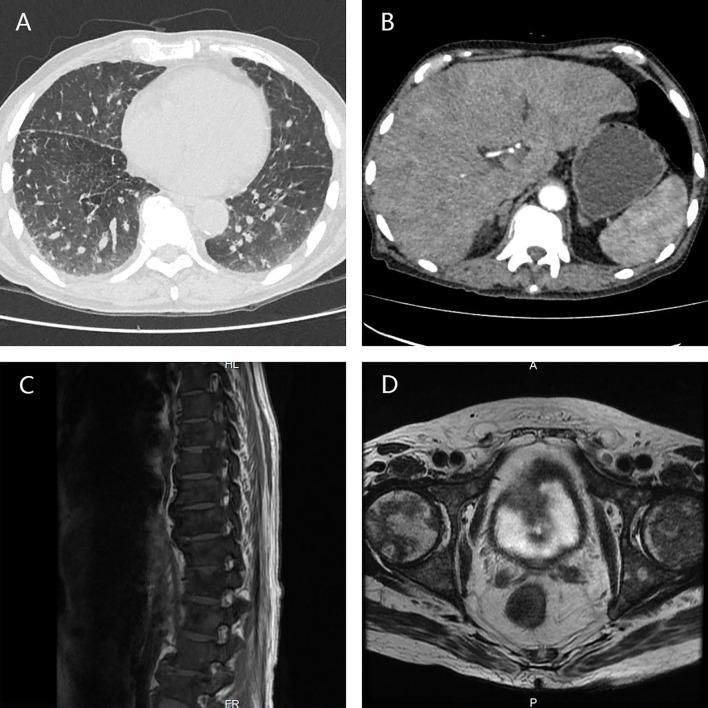

A 57-year-old man with metastatic PCa had been managed by Dr. J.P. since April 2012 when the patient was admitted to the Third Affiliated Hospital of Sun Yat-sen University by aggravating frequent urination and dysuria. The prostate-specific antigen (PSA) concentration was 140 ng/ml, and the diagnosis of PCa was confirmed by prostate biopsy, with Gleason score 4 + 5 = 9. Chest CT and bone scan indicated multiple metastases in the lungs and bones. Triptorelin, bicalutamide, zoledronic acid, and docetaxel were then administered, six cycles later, the metastatic tumors in the lungs disappeared and those in the bones lessened significantly, along with a remarkable reduction in PSA level (< 2 ng/ml). Intermittent androgen deprivation was subsequently conducted until August 2018, when the serum PSA level was found to be 250 ng/ml, again docetaxel 75 mg/m was administered immediately but the patient was intolerant this time. Instead, abiraterone was administered until March 2019 because of intolerable gastrointestinal side-effects and increasing PSA level. In October 2019, the patient came to our center, a modified approach of docetaxel (day 1 40 mg/m + day 8 35 mg/m) was administered. Luckily, the PSA level decreased rapidly, the bone pain was greatly relieved, and no obvious side effects occurred. However, four cycles later, docetaxel failed to work anymore, the metastatic tumor in the liver progressed. We proposed several regimens as alternatives, but they were soon denied due to the high prices or unavailability or uncertain effect of the drugs. In addition, the patient's condition deteriorated speedily and can no longer bear any aggressive treatment. Finally, the patient died of multiple organ failure in August 2020.

一名患有转移性PCa的57岁男性自2012年4月起由J.P.医生负责治疗,当时患者因尿频和排尿困难加重而入住中山大学附属第三医院。前列腺特异性抗原(PSA)浓度为140 ng/ml,经前列腺活检确诊为PCa,Gleason评分为4 + 5 = 9。胸部CT和骨扫描显示肺部和骨骼有多处转移。随后给予曲普瑞林、比卡鲁胺、唑来膦酸和多西他赛,六个周期后,肺部的转移瘤消失,骨骼中的转移瘤明显缩小,PSA水平显著降低(< 2 ng/ml)。随后进行间歇性雄激素剥夺治疗,直到2018年8月,发现血清PSA水平为250 ng/ml,再次立即给予75 mg/m的多西他赛,但患者这次不耐受。相反,由于无法耐受的胃肠道副作用和PSA水平升高,给予阿比特龙治疗直至2019年3月。2019年10月,患者来到我们中心,给予改良的多西他赛方案(第1天40 mg/m + 第8天35 mg/m)。幸运的是,PSA水平迅速下降,骨痛大大缓解,且未出现明显副作用。然而,四个周期后,多西他赛不再起作用,肝脏中的转移瘤进展。我们提出了几种替代方案,但由于药物价格高、无法获得或效果不确定而很快被否定。此外,患者的病情迅速恶化,无法再承受任何积极的治疗。最后,患者于2020年8月死于多器官功能衰竭。